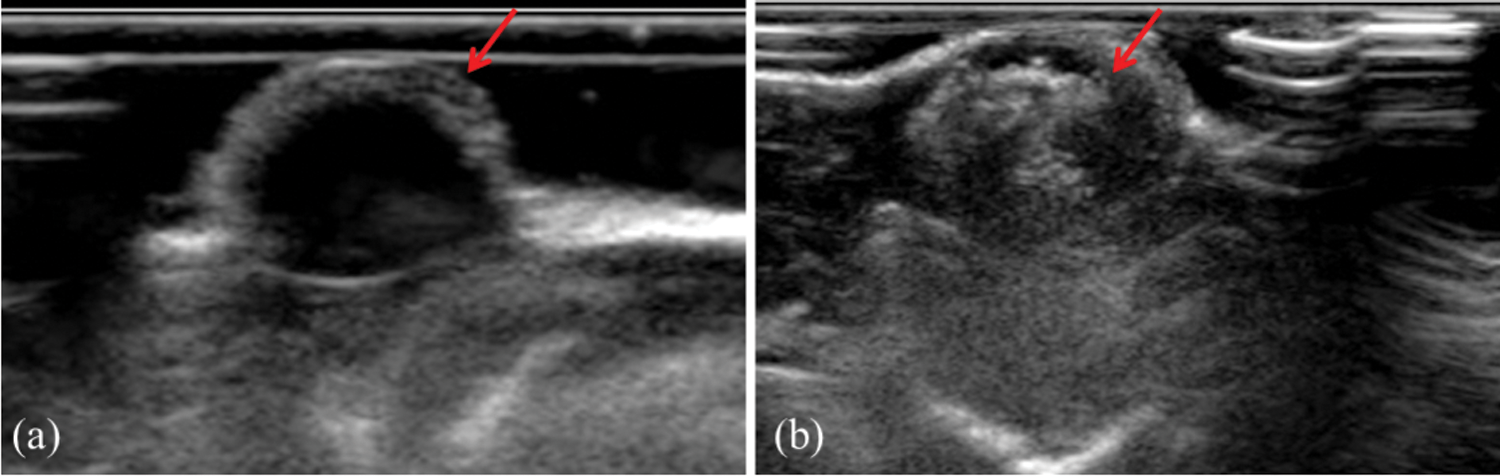

3.6 Ultrasonic Imaging in Vivo

To evaluate the tumor enhanced ultrasound imaging capability of PFP/Lf-PLLA NBs in vivo, subcutaneous tumor animal models were constructed. As shown in Fig. 7a, before the administration of PFP/Lf-PLLA NBs, the area of the tumor was hypoechoic and dark region, and exhibited a blurred boundary with the surrounding tissue. However, when the PFP/Lf-PLLA NBs suspension was injected, there were obvious bright spots throughout the subcutaneous tumors, the gray-scale intensity increased and marked ultrasound imaging enhancement occurred immediately, the results were shown in Fig. 7b. The enhancement obtained using nanobubbles lasted for approximately 1.5 h, indicating that the PFP/Lf-PLLA NBs were stable and long-lasting contrast ability enough for clinical ultrasonography.

Figure 7: The effect of PFP/Lf-PLLA NBs on tumor imaging in vivo. (a) pre- and (b) post-injection of PFP/Lf-PLLA NBs